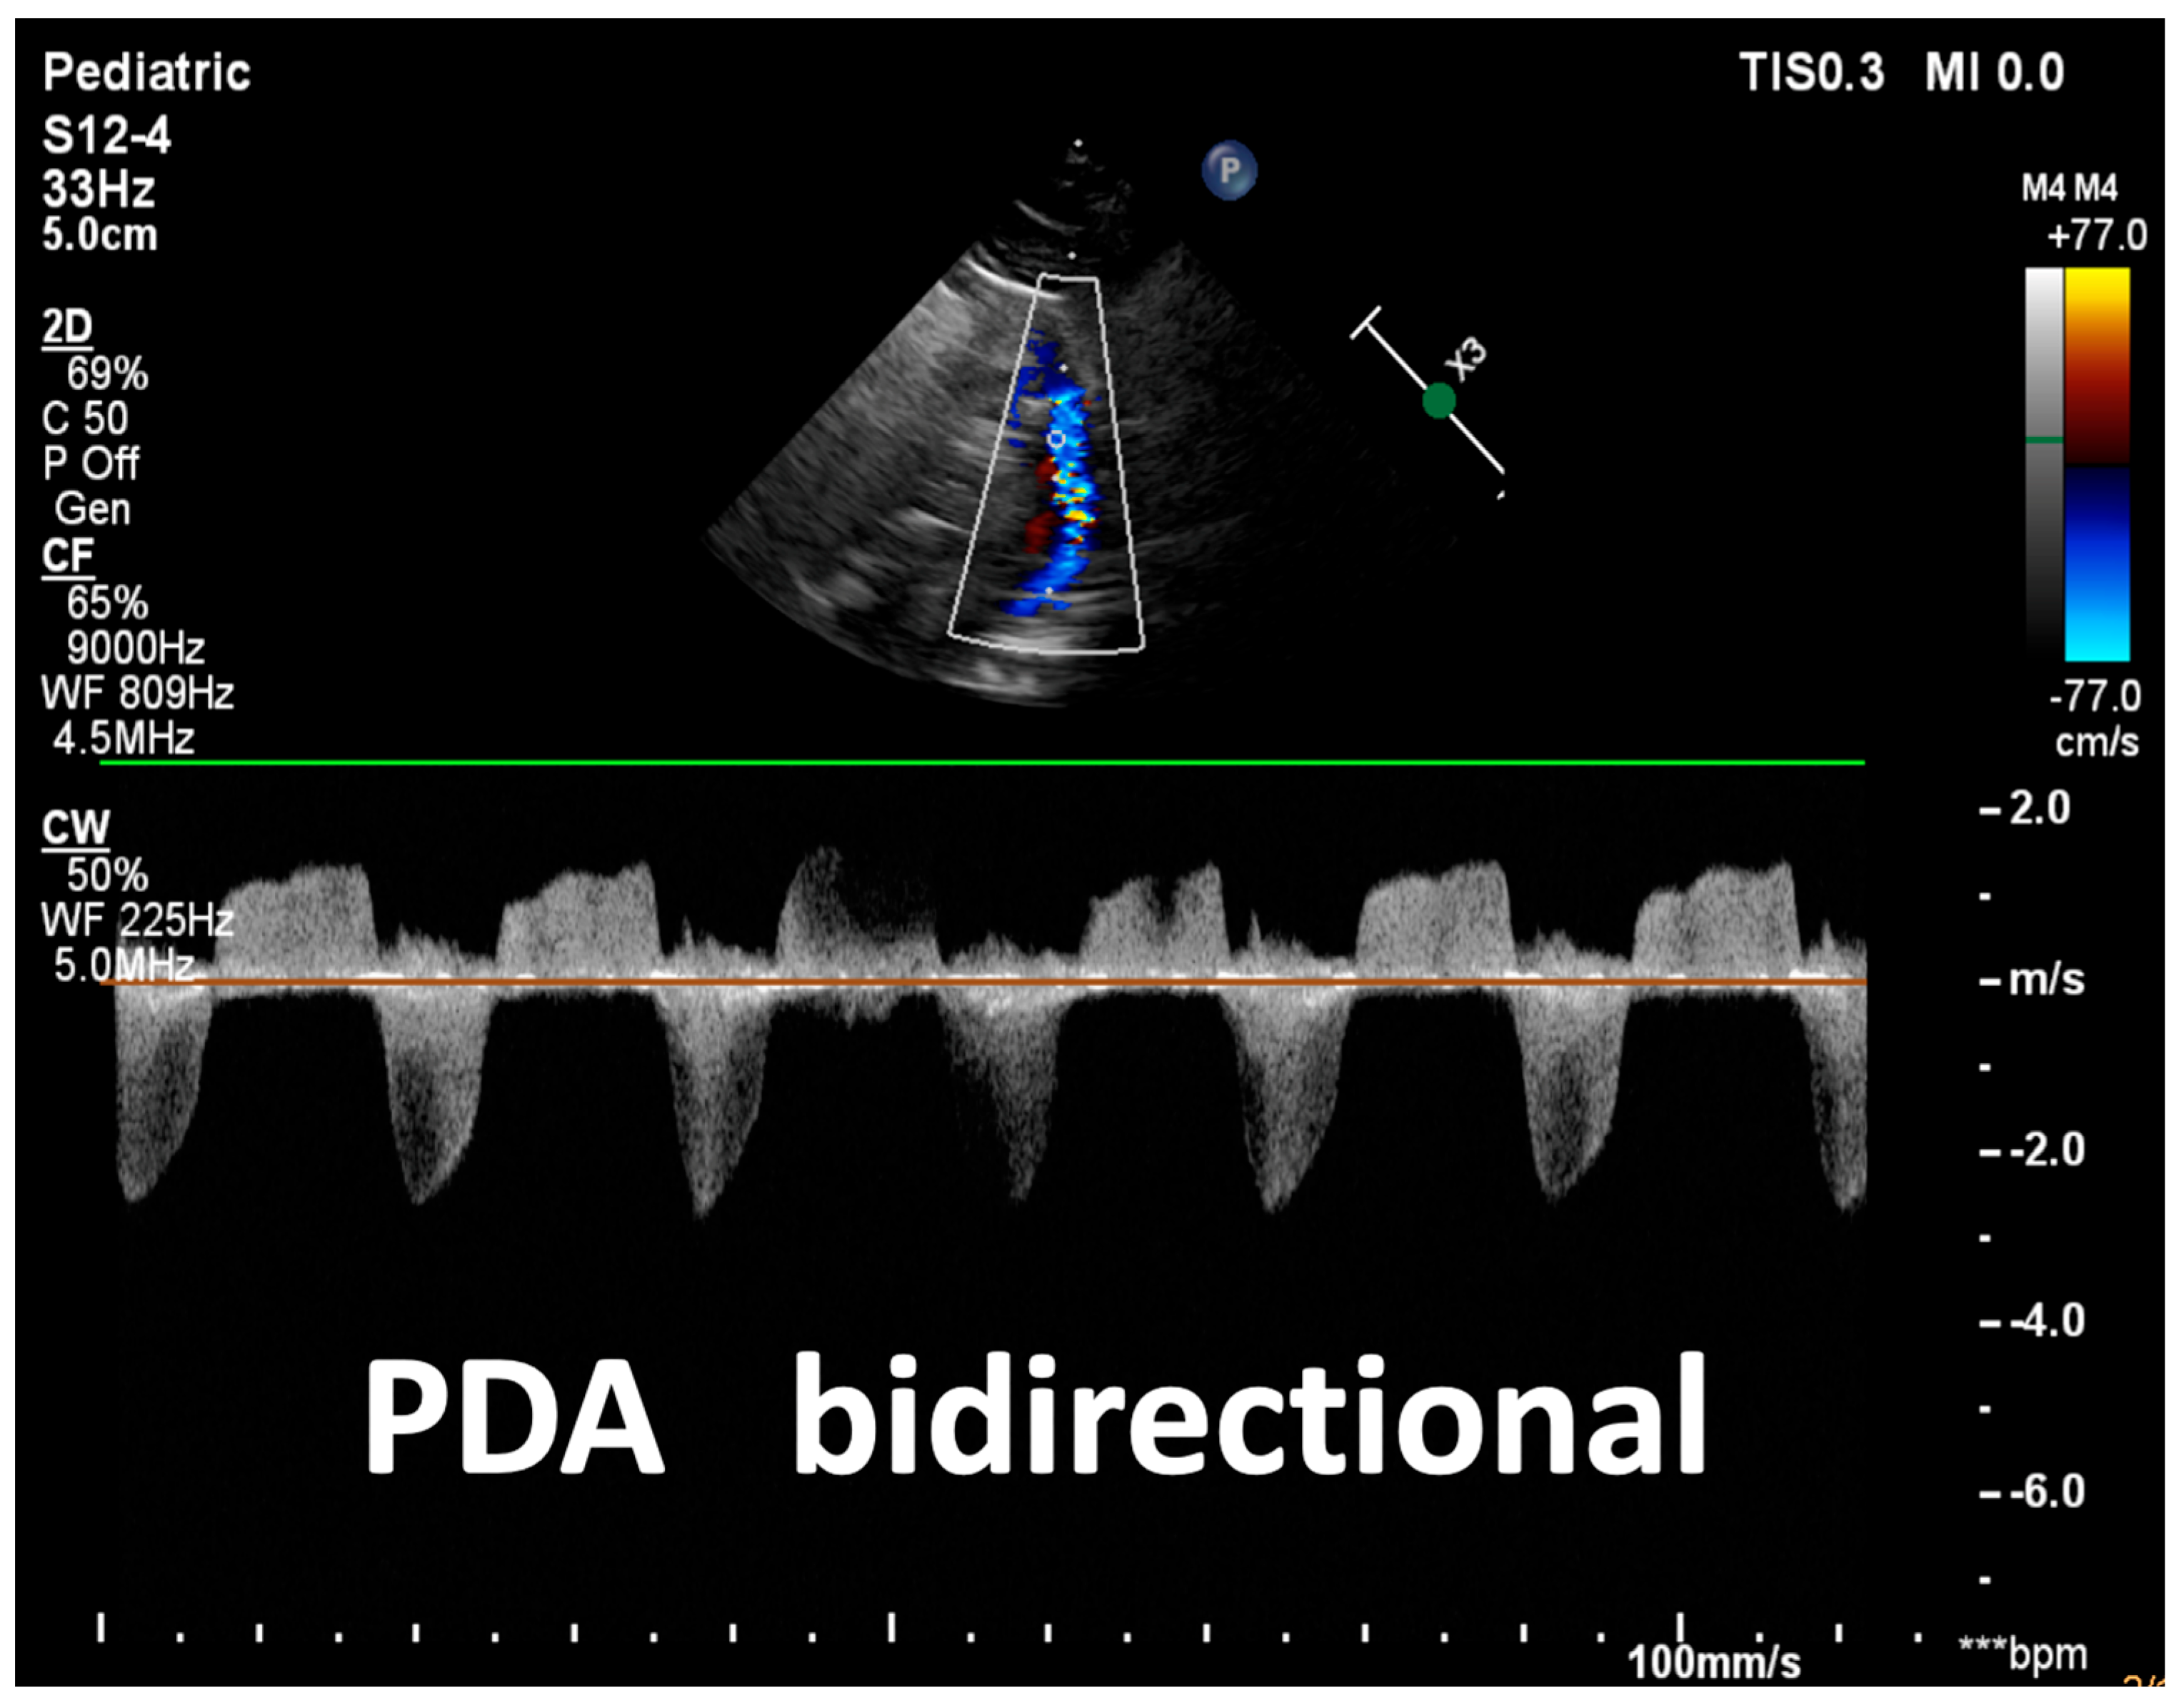

| Detection of Shunt | Identification and assessment of flow through the patent foramen ovale (PFO) and ductus arteriosus (PDA) | Indicates the presence and nature of pathological flow: left-to-right, bidirectional (often in moderate PPHN), or right-to-left (in very severe PPHN) |